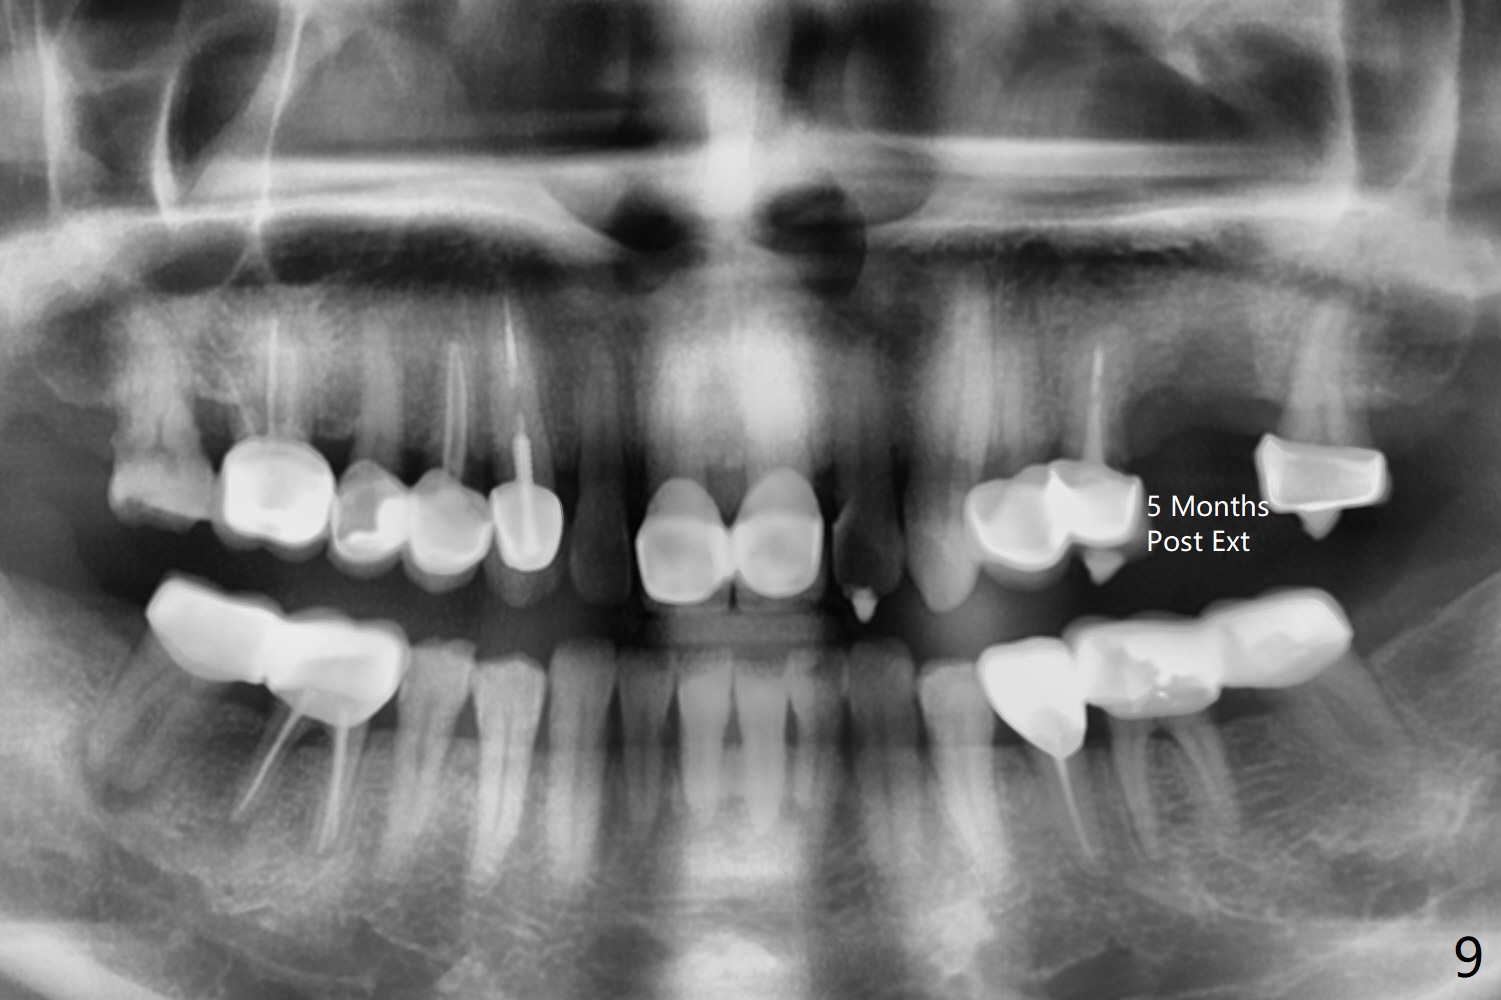

A 49-year-old woman returns for removal of the tooth #14 with loss of the buccal plate (Fig.1 red dashed line). After extraction, the buccal gingiva collapses as a dimple (Fig.2 ^). Cytoplast, a Titanium-Reinforced Non-resorbable Membrane (Fig.3), is used after bending (Fig.4) to assist in repair of the buccal plate with bone graft (Fig.5,6). As compared to Fig.1, the bone height also increases. Periodontal dressing and Cytoplast dislodge with odor 10 days postop (Fig.7,8). Periodontal dressing is re-applied. Spacer or acrylic dressing should have been used for security. In spite of the narrow ridge 5 months postop (Fig.9), a 5x11.5 mm bone level or 5x17 mm tissue-level implant is possible (Fig.10). But the implant should be placed more palatal, away from the buccal defect!